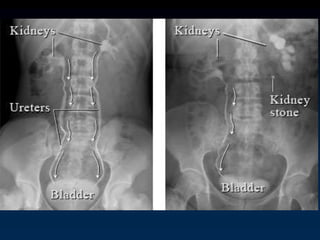

Differential Diagnosis Back Pain

Not from the Spine

 UTI

 Abdomen (cholecystitis, pancreatitis, aortic

aneurysm, peptic ulcer disease, nephrolithiasis,

pelvic inflammatory disease, diverticulitis)